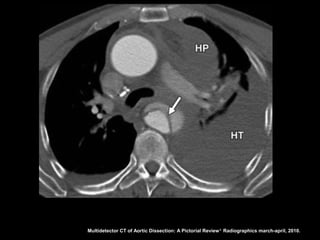

Multidetector CT of Aortic Dissection: A Pictorial Review 1. Radiographics march-april, 2010.

Definição da luz

•A luz falsa com frequência tem área transversal

maior devido ao fluxo lento;

• A luz verdadeira encontra-se comprimida em 80%

dos casos;

• A falsa luz tem maior propensão à trombose;

• Quando uma luz envolve a outra, a luz interna

invariavelmente é a verdadeira;

• O fluxo sanguíneo lento leva a retardo na

opacificação da luz falsa.